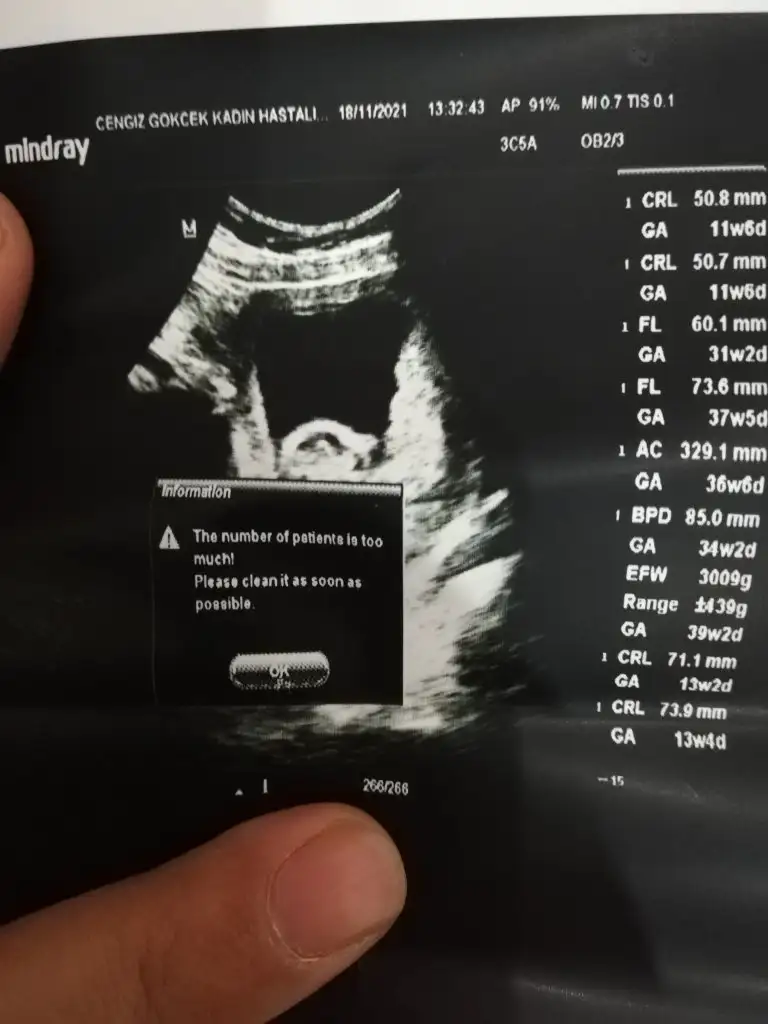

Canım bizde 13 haftalık olduk geldik bakar mısın

Erkek sankiİkra hanım merhaba 12 hafta görüntülerini ekledim sizce nedir cinsiyeti

Erkek ve kız için 11 + 12+ yada 13 hafta usg görüntüsü olmalı açıklamalar asagıda yazıyorrabbim herkesin gönlüne göre nasip etsin inşallah .. ecmain